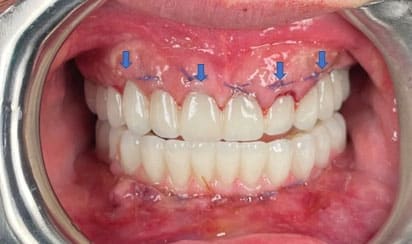

Minimally Invasive

Our EXPERIENCE and METHOD give our patients faster RECOVERY time.

Custom-Made (OUR)

Match to Existing Natural Gum Tissue

Minimal Invasive Surgery